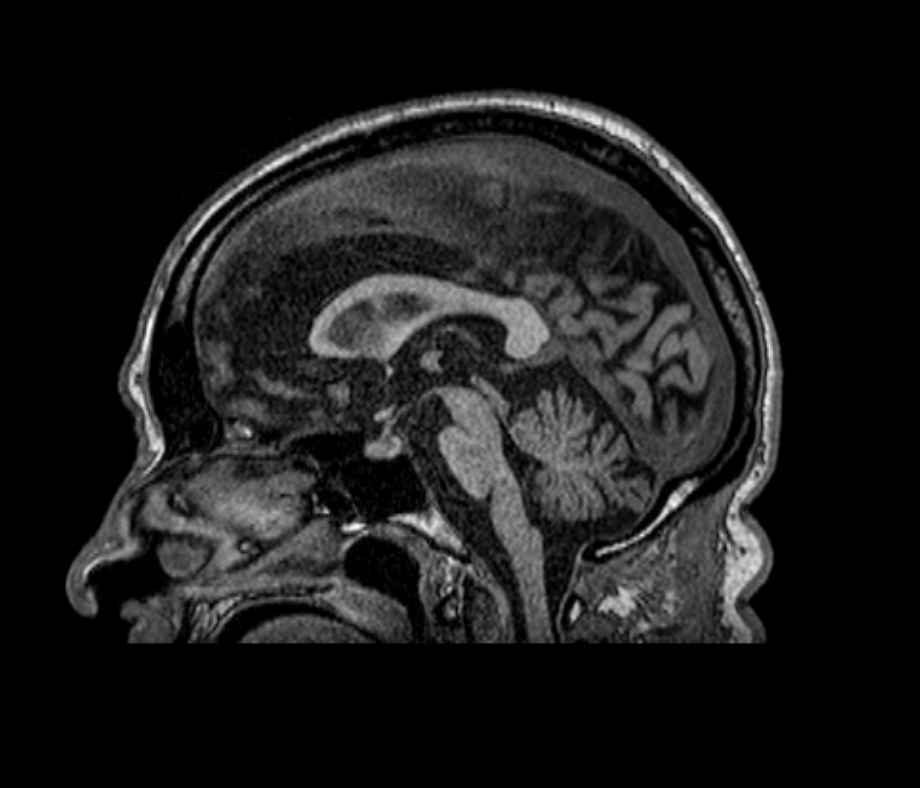

Results: A 65 year old male patient with just a past history of smoking who presented to the neurology consult with a 5 year history of slow progressive gait instability, dizziness. sexual dysfunction and urinary incontinence. His neurological examination revealed an ataxic gait, with right rigidity and bilateral dysmetria and bradykinesia. Laboratory work up revealed negative infectious and rheumatologic tests, a hyperproteinorrachia with no pleocytosis in CSF, a normal Dat Scan, and a brain MRI with severe pons, middle cerebellar peduncles and cerebellar atrophy (figure 1 and 2). Paraneoplastic panel was positive in two different samples for Yo-1 antibodies. Screening for underlining neoplasia was negative for breast, lung, gastric and prostate cancer. The patient received a 5 days cycle of IV immunoglobulin with a marked improvement in his gait, balance and limb symptoms.

Figure2. Cerebellar and pons atrophy.